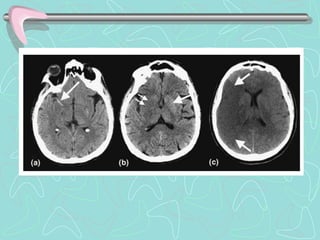

PENUMBRA ISQUEMICA Core andpenumbra in acute stroke imaging. The infarct core, presumptively identified by an abnormality in a DWI image, represents tissue that cannot be salvaged. The ischemic penumbra represents tissue that is threatened by ischemia, but may still be saved by timely therapy. The penumbra is presumptively identified as that tissue that is normal in early DWI images, but abnormal in maps of CBF.

• 42.

PENUMBRA ISQUEMICA (a) EarlyDWI image shows several small closely clustered acute infarcts in the left corona radiata. An MTT map (b) shows a much larger region of impaired perfusion, theoretically representing tissue at risk. However, a follow-up T2-weighted FLAIR image (c) shows that the infarct has not grown substantially. Preservation of penumbral tissue, as demonstrated by this case, … is the goal of acute stroke therapy.